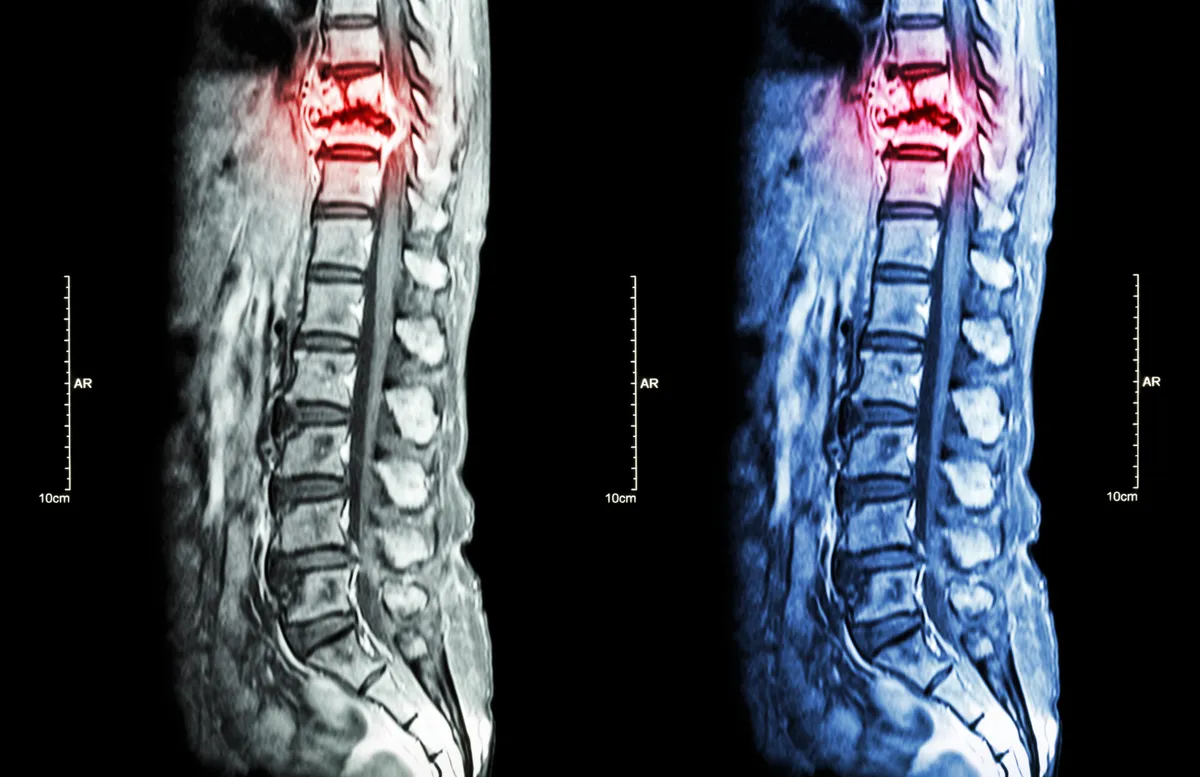

MRI-Based Biomarkers

Advanced imaging techniques for injury assessment and prognosis prediction